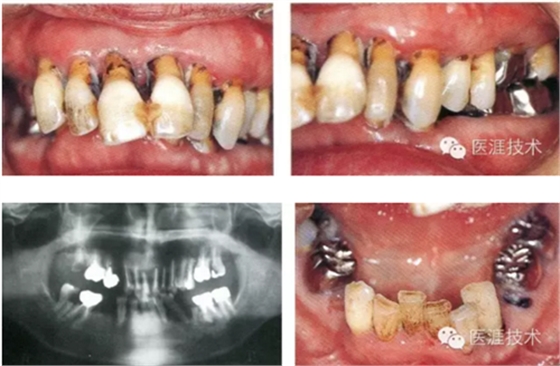

女性 58歲

主訴:咀嚼無(wú)力,有口臭,有胃病,經(jīng)常感覺(jué)全身無(wú)力。

01,初診檢查狀態(tài)